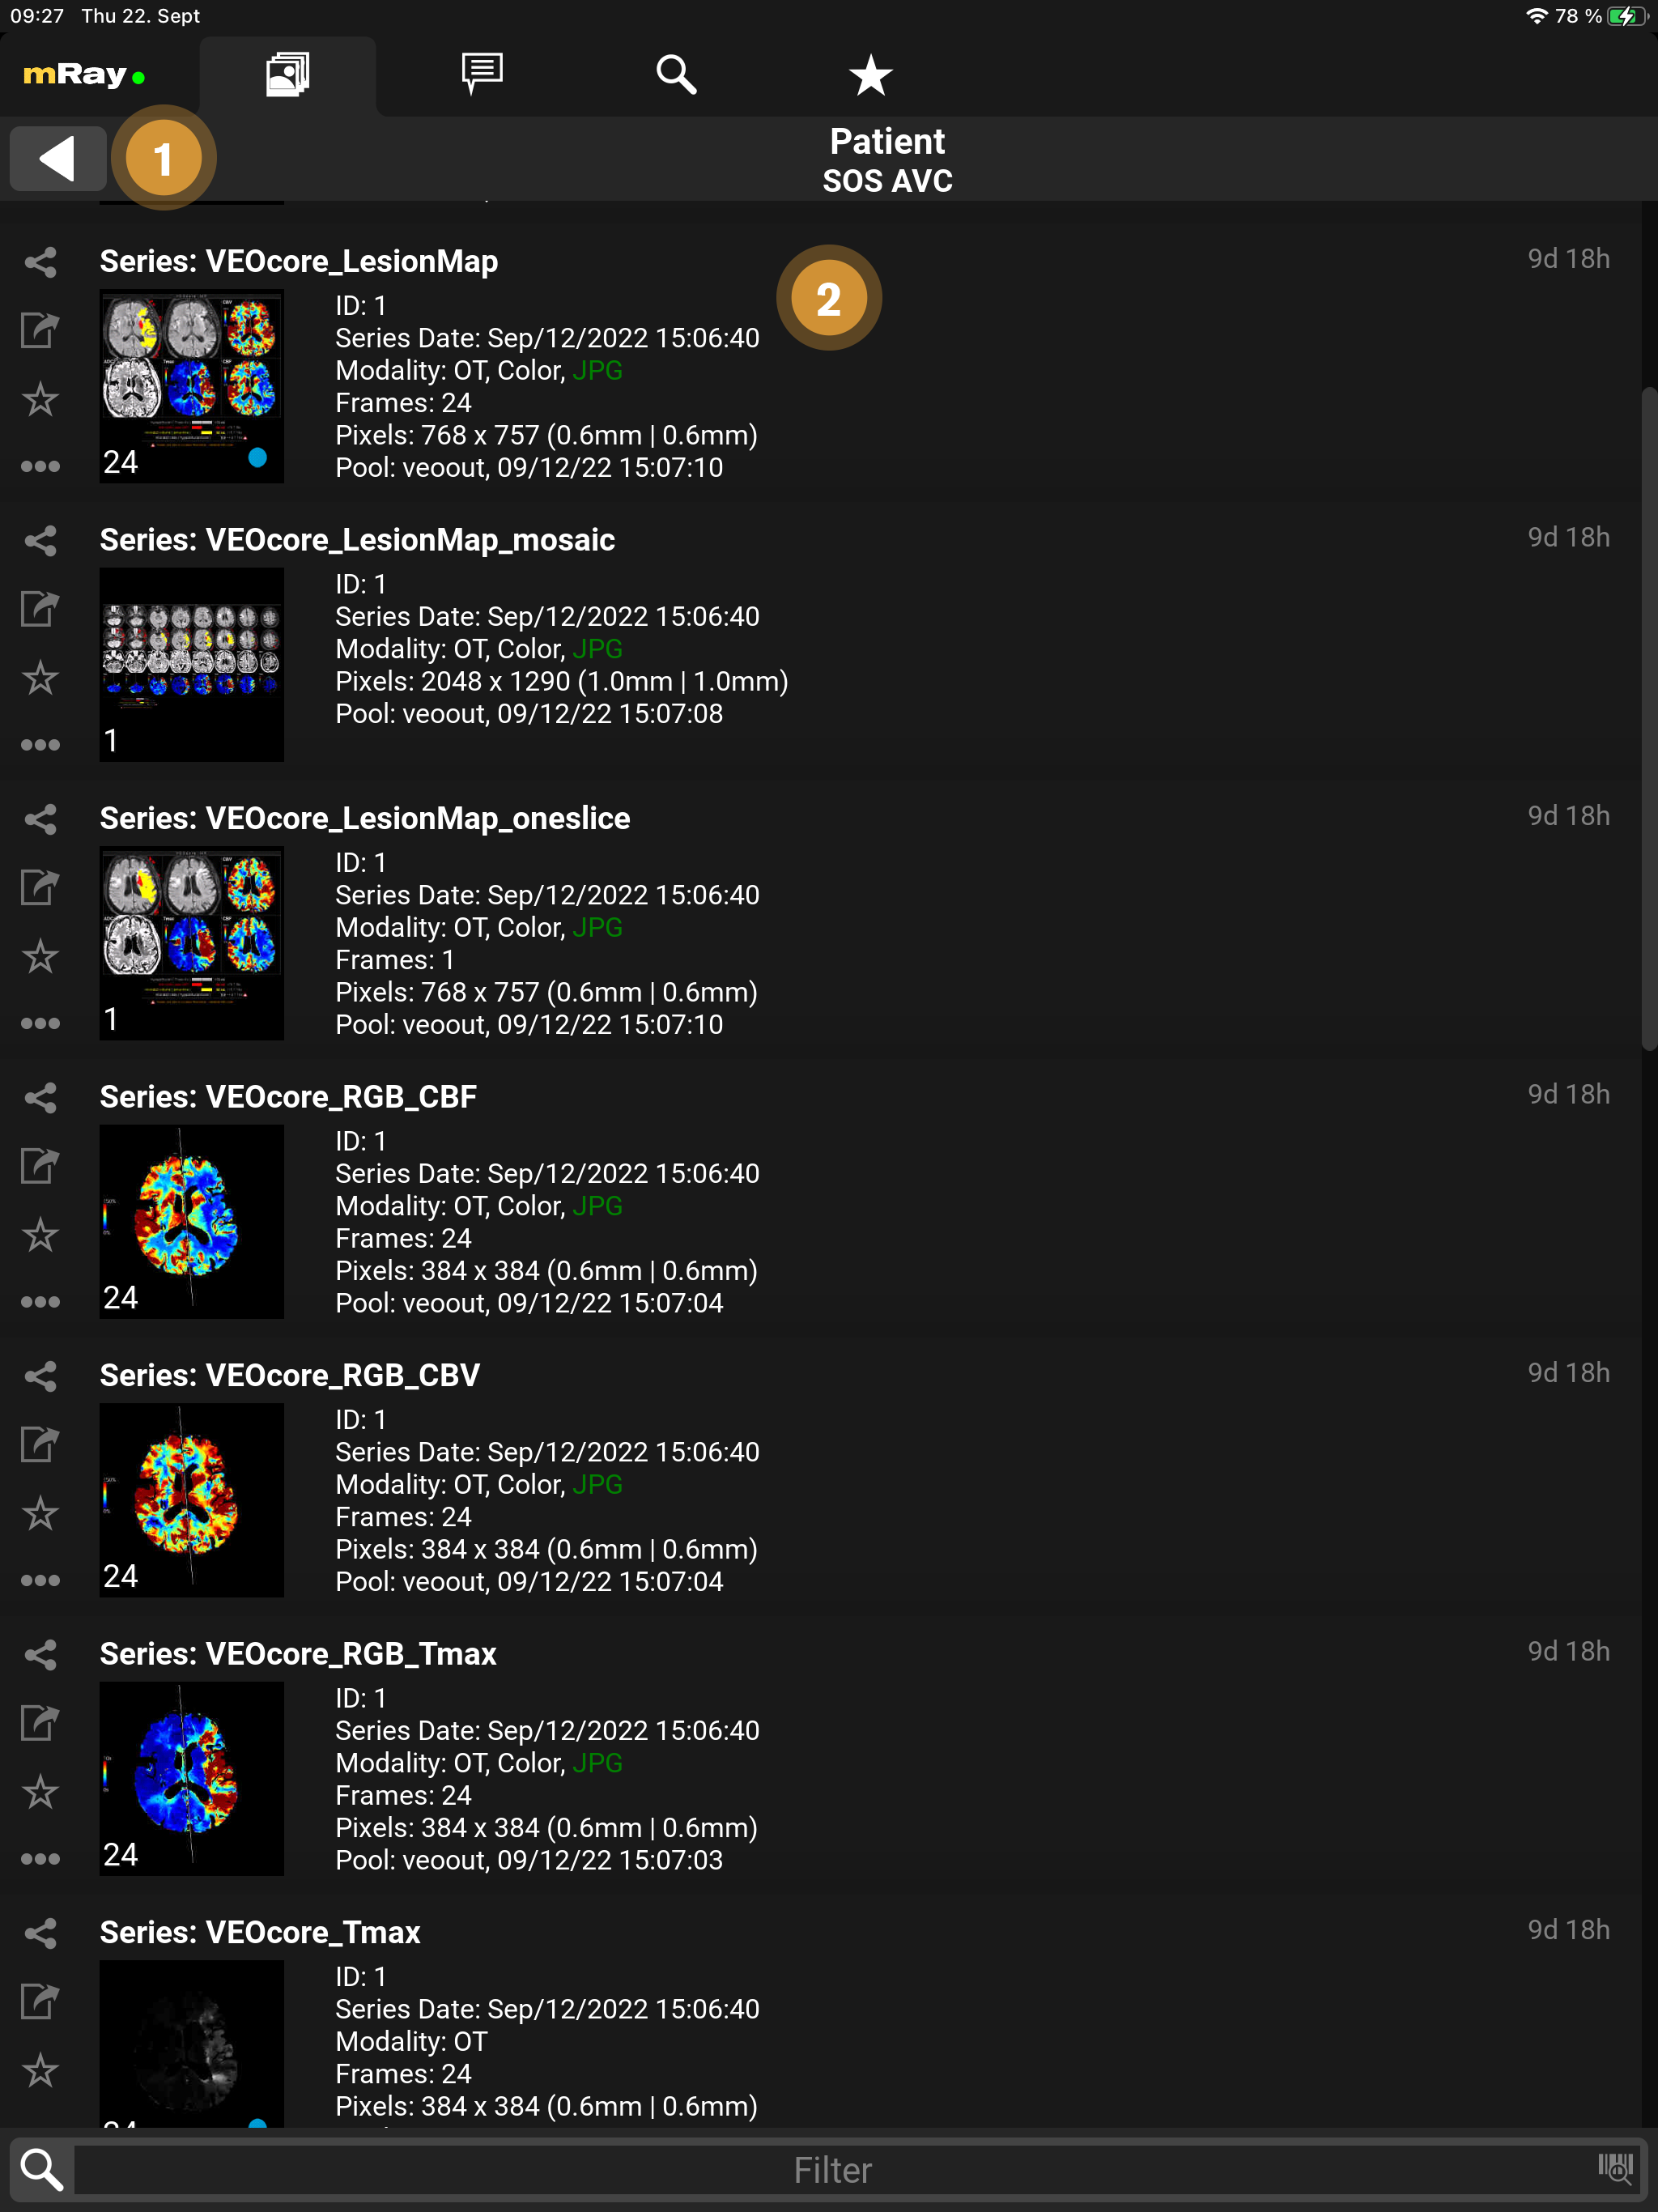

9.2. Series selection

-

Datasets: Enumeration of all recorded images of the study of a patient.

By clicking a series it will be downloaded (if it’s not already downloaded) and opened for viewing.

9.2.2. Series details

More details about a series can be foun the series selection list.

Pool: name of pool; time when the series was available in mRay; transfer time from PACS to mRay